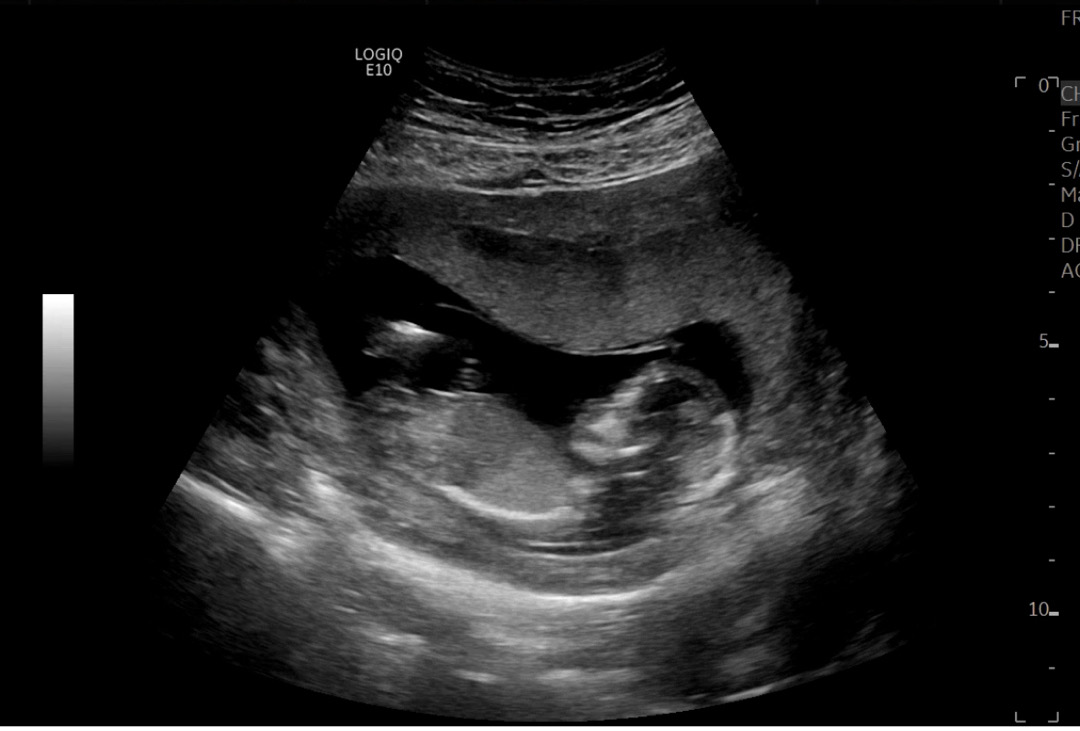

성별질문13주0일각도법

빌리에선딸이라고하는데 알수 있을까요???

음..딸인것 같아요!!